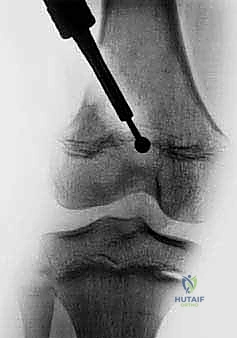

1. الأشعة السينية (X-rays)

تعتبر الخطوة الأولى. يمكن للأشعة السينية إظهار التشوه الزاوي، وخطوط توقف النمو (Harris growth arrest lines). إذا كانت هذه الخطوط مائلة وليست متوازية مع صفيحة النمو، فهذا دليل قاطع على وجود عائق عظمي غير متماثل.